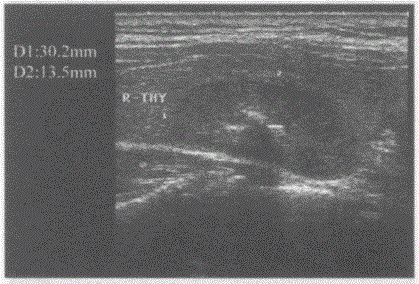

问题 临床资料:女,40岁,自诉右侧颈部不适. 临床物理检查:右颈部可扪及一肿物,边界清晰,可随吞咽上下移动。 超声综合描述:甲状腺右叶中部可见3.0cm×1.4cm不均质回声区,内可见数个强回声光团,最大直径0.4cm,后伴声影,CDFI:不均回声内血供丰富。见下图及彩图。 {图1} 超声提示:

选项 A.甲状腺癌(右叶) B.甲状腺腺瘤合并钙化(右叶) C.结节性甲状腺肿 D.甲状腺钙化灶(右叶)

答案 B